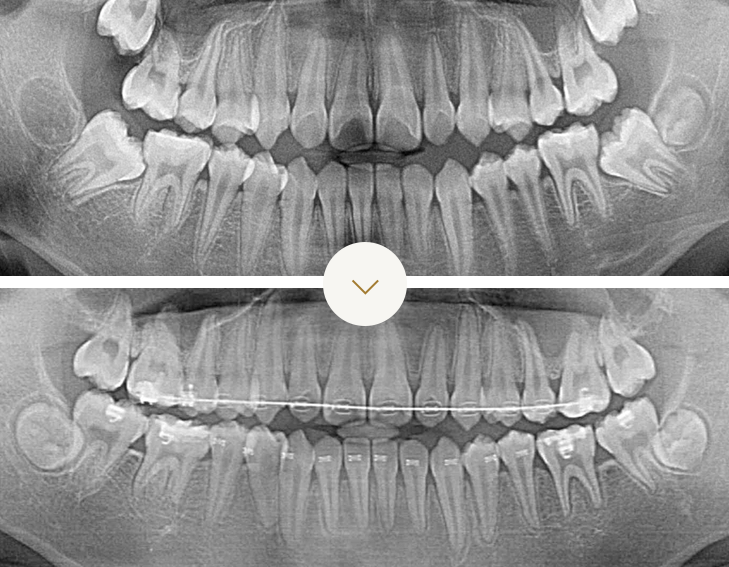

영구치 맹출이상 성장교정

전후 사례

적절한 시기에 양쪽 위유치송곳니를 제거하였기 때문에 위송곳니가 제대로 내려오는 모습입니다

Step 01

Step 02

After

Before & After